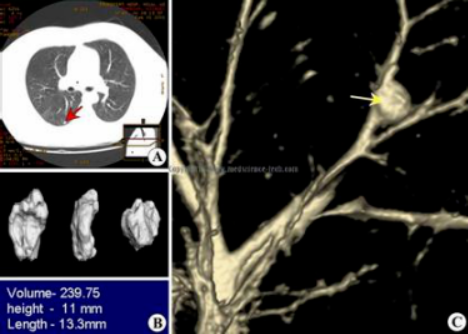

据说,每3个“健康人”做胸部CT

就会有1人查出肺结节